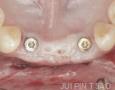

2 Years

3 Years